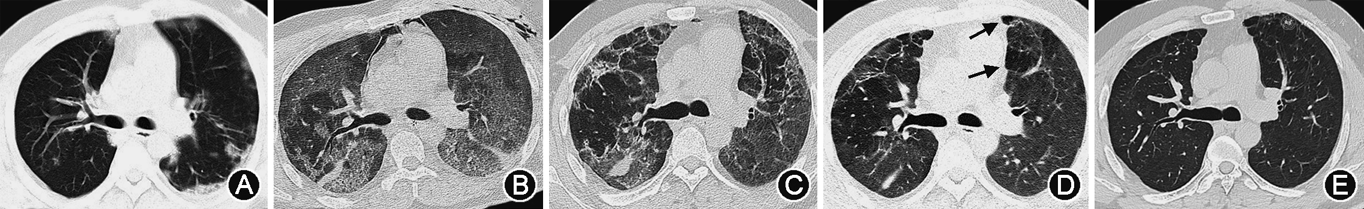

1. 重症病例:(1)X线:双肺受累多见,多发生在下肺[11, 12]。双肺纹理模糊,局限性或弥漫性分布的磨玻璃样改变及实变,部分可见弥漫性网状或结节状阴影。病程进展,病灶范围扩大,单侧病变可进展为双侧病变,单灶或多灶病变可进展为弥漫性病变,磨玻璃改变可融合为大片状实变[13]。可伴有胸腔积液[13]。合并肺气肿时,在病毒性肺炎基础上可见肺野透光度增强;合并细菌性肺炎时,表现为局灶性片状高密度影(图1)。(2)CT:单纯甲型H1N1流感重症肺炎病变常累及多个肺段及肺叶,病变可随机分布,但以双肺中下部周边为主[14, 15, 16, 17]。病变多表现为GGO和实变,或二者混合存在。磨玻璃阴影多位于周边,实变多靠近肺门,其内可见空气支气管征[18, 19, 20, 21](图1、2)。随病情进展,GGO会转化为实变,实变吸收也会转变成GGO。此外,还可见支气管血管束增粗、牵拉性支气管扩张等表现[16,22, 23](图3)。小叶间隔增厚、小叶中心结节等表现由于病情进展常常被掩盖,恢复期可见[24]。肺门及纵隔淋巴结肿大、胸腔积液和胸膜增厚等表现相对少见[25, 26]。肺栓塞亦可见,且发生风险较高[11,27]。可合并其他细菌性肺炎,进而形成合并性影像表现[12, 13,17]。治疗后恢复吸收阶段,病灶大多数可吸收,呈肺内广泛条索状、斑片状改变,甚至消失,部分病灶残留纤维瘢痕[22, 23]。

2. 危重病例:多表现为大片状或弥漫性病灶,在重症病例影像表现基础上,以实变为主,也可以合并肺不张和“白肺”改变[13,15, 16, 17,23,28, 29],少数病例可见胸腔积液[25, 26]。病程多进展较快,需要机械通气,继发纵隔气肿、皮下气肿及气胸[11,23,30](图4、5)。同时也常常合并其他感染及并发症,如肺栓塞等[11,30]。